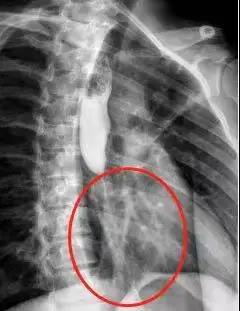

最终,经过三次手术后,小蔡吞咽不畅的情况完全消失。

小蔡如今的食管